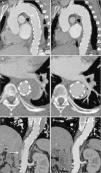

Para despiste de patologia da aorta, realizou‐se angiotomografia computorizada (angioTC) do tórax que evidenciou dilatação ligeira da aorta ascendente (diâmetro máximo de 42mm) e um espessamento circunferencial da parede da aorta (de aproximadamente 10mm), compatível com IMH, com início imediatamente após a origem da artéria subclávia esquerda e envolvendo toda a aorta descendente e porção proximal da aorta abdominal, até ao nível da emergência das artérias renais (figura 1). Além disso, evidenciava‐se também a presença de canal arterial patente tipo A (figura 1B) e na região proximal da aorta descendente duas ulcerações da parede e uma placa aterosclerótica parcialmente calcificada (figura 1B e C).

Imagens da primeira angioTC efetuada, onde se observa o espessamento circunferencial da parede da aorta (setas), compatível com hematoma intramural, com início imediatamente após a origem da artéria subclávia esquerda e envolvendo toda a aorta descendente e porção proximal da aorta abdominal (imagem A); imagem B – canal arterial patente (ponta de seta) e uma placa aterosclerótica parcialmente calcificada (seta); imagem C – as setas destacam duas ulcerações da parede da aorta descendente proximal.